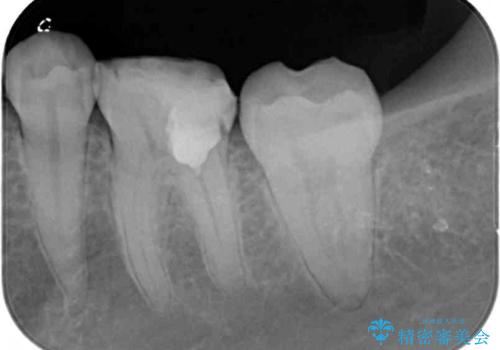

処置開始前から神経組織を部分的に除去する可能性が高いことが分かっていたため、ラバーダムなどの環境を整え、無菌的環境下にて処置を進めて行きました。

虫歯は深くまで進行しており、歯冠部後方の神経から出血が認められました。炎症を起こしている神経を除去したところ出血が治まったので、生体親和性の非常に高いセメントにて充填し、仮封をし、その日のうちに仮歯を装着しました。